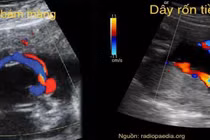

(khoahocdoisong.vn) - Phát hiện tiền sản về bất thường dây rốn qua siêu âm hiện đang trở nên phổ biến với những tiến bộ sản khoa. Siêu âm sản khoa 2 chiều, 3 và 4 chiều và Doppler như một công cụ để đo lường và đánh giá hình thái của dây rốn có giá trị trong sàng lọc đối với thai kỳ có nguy cơ cao.